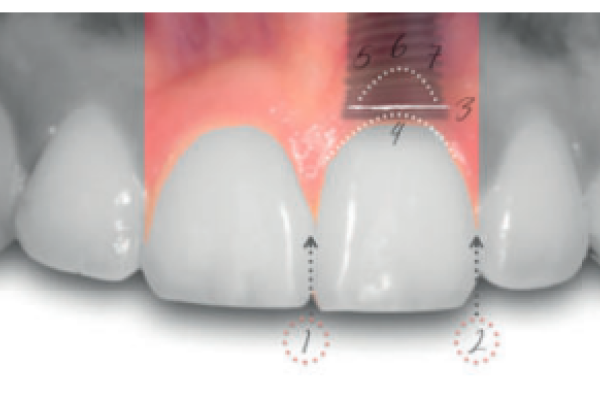

8 | ARTÍCULO ORIGINAL | ANÁLISIS DE LOS TEJIDOS PERI-IMPLANTARIOS EN IMPLANTES ANTERIORES: RELACIÓN ENTRE LA PRESENCIA O AUSENCIA DE TABLA ÓSEA Y EL PINK ESTHETIC SCORE |